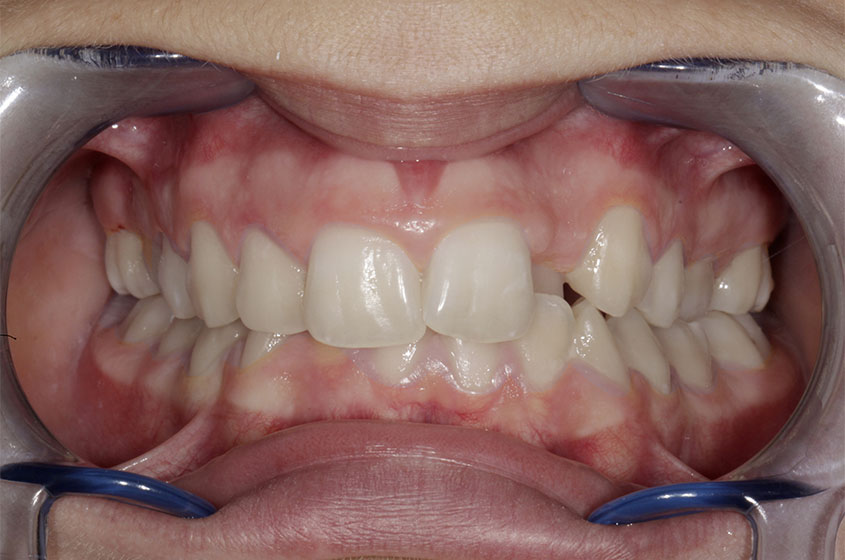

https://sorridibene.etweb.it/wp-content/uploads/2020/07/2-1.jpg

Buona occlusione

Questa è una buona occlusione! In una occlusione ottimale, ogni dente occlude con l’antagonista e con il dente adiacent...